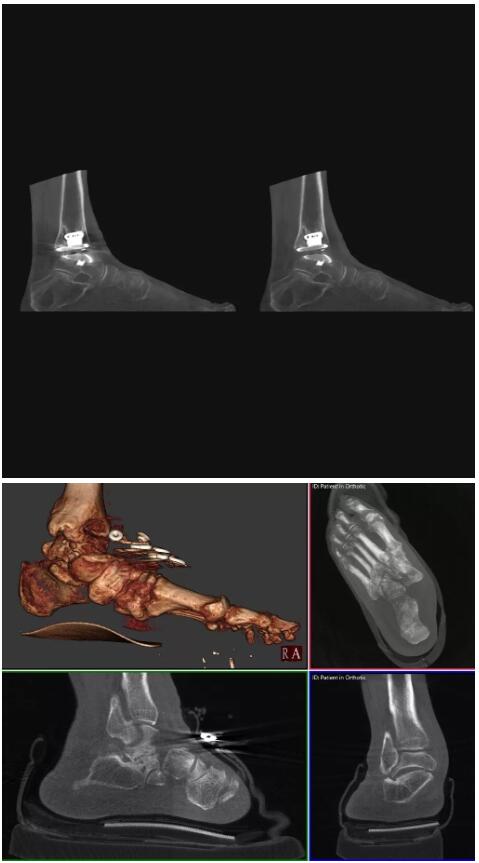

比如上面這款專用于足部和踝部掃查的CT成像系統(tǒng),患者在進行CT掃查時只需要站在上面即可,雙腳站或者單腳站都可以,當(dāng)然,如果患者不是那么方便站著做完CT掃查,也可坐在上面。

這款CT掃查系統(tǒng)自帶屏蔽裝置,它的體積非常小,僅需要極小的空間即可,并不像常規(guī)CT那樣需要一間單獨的檢查室。此外,這種CT掃查的速度非???,僅需30秒左右可以完成檢查,輻射劑量相對常規(guī)的CT要少許多,尤其適合醫(yī)院的骨科使用。

而患者站著做足部或者踝部做CT檢查還有個好處是,可以檢查患者在負(fù)重的情況下,骨關(guān)節(jié)的真實情況,而躺著做CT掃查時未必能看出來。負(fù)重CT掃查特別是對于受傷的運動員或者舞蹈員來說意義更大,能夠更準(zhǔn)確地評估傷情,幫助他們盡早復(fù)原。

以下是這些“特立獨行”的CT所拍出來的圖像: